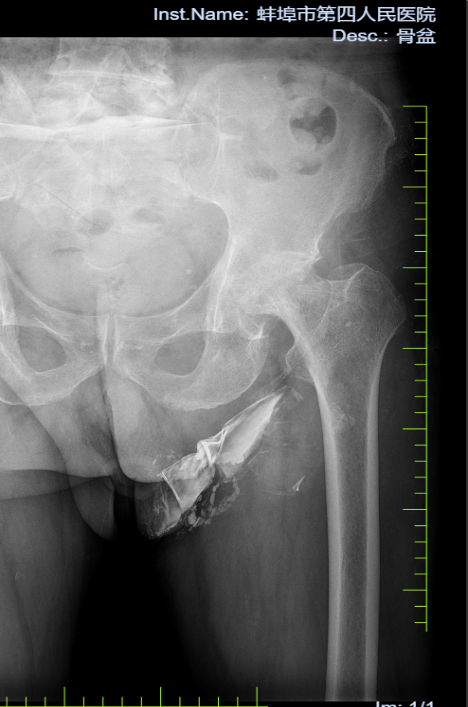

病例二:患者,女,84岁,因“摔伤致左髋部疼痛伴活动受限3天”入院。诊断:左侧股骨颈骨折;行左侧人工股骨头置换术,手术顺利,术后恢复良好,顺利出院。

左侧股骨颈骨折 术前X线片 左侧股骨颈骨折 术后X线片